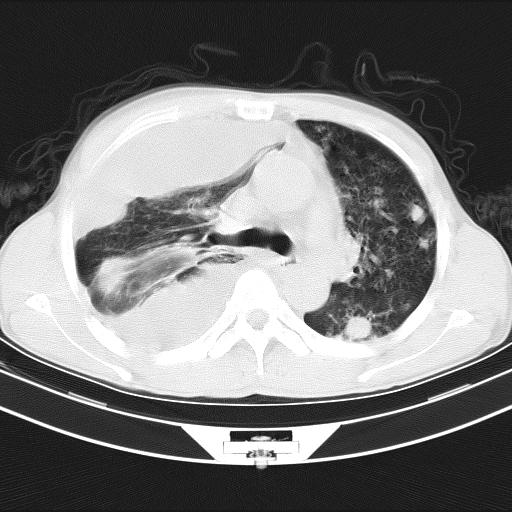

男性,44岁,结核病史多年。现胸闷气短,咳嗽,偶咳血。

右侧胸腔积液

右肺下叶不张

双肺多发结节影最分空洞形成考虑占位不除外结核

双肺陈旧性病变

1、右侧大量胸腔积液伴右肺压缩性膨胀不全,建议抽液治疗后复查 2、两肺继发性tb伴空洞形成。

1)两肺继发性肺结核伴空洞形成,左肺多发性结核球。2)右侧大量胸腔积液伴右肺部分膨胀不全。3)纵隔淋巴结肿大。